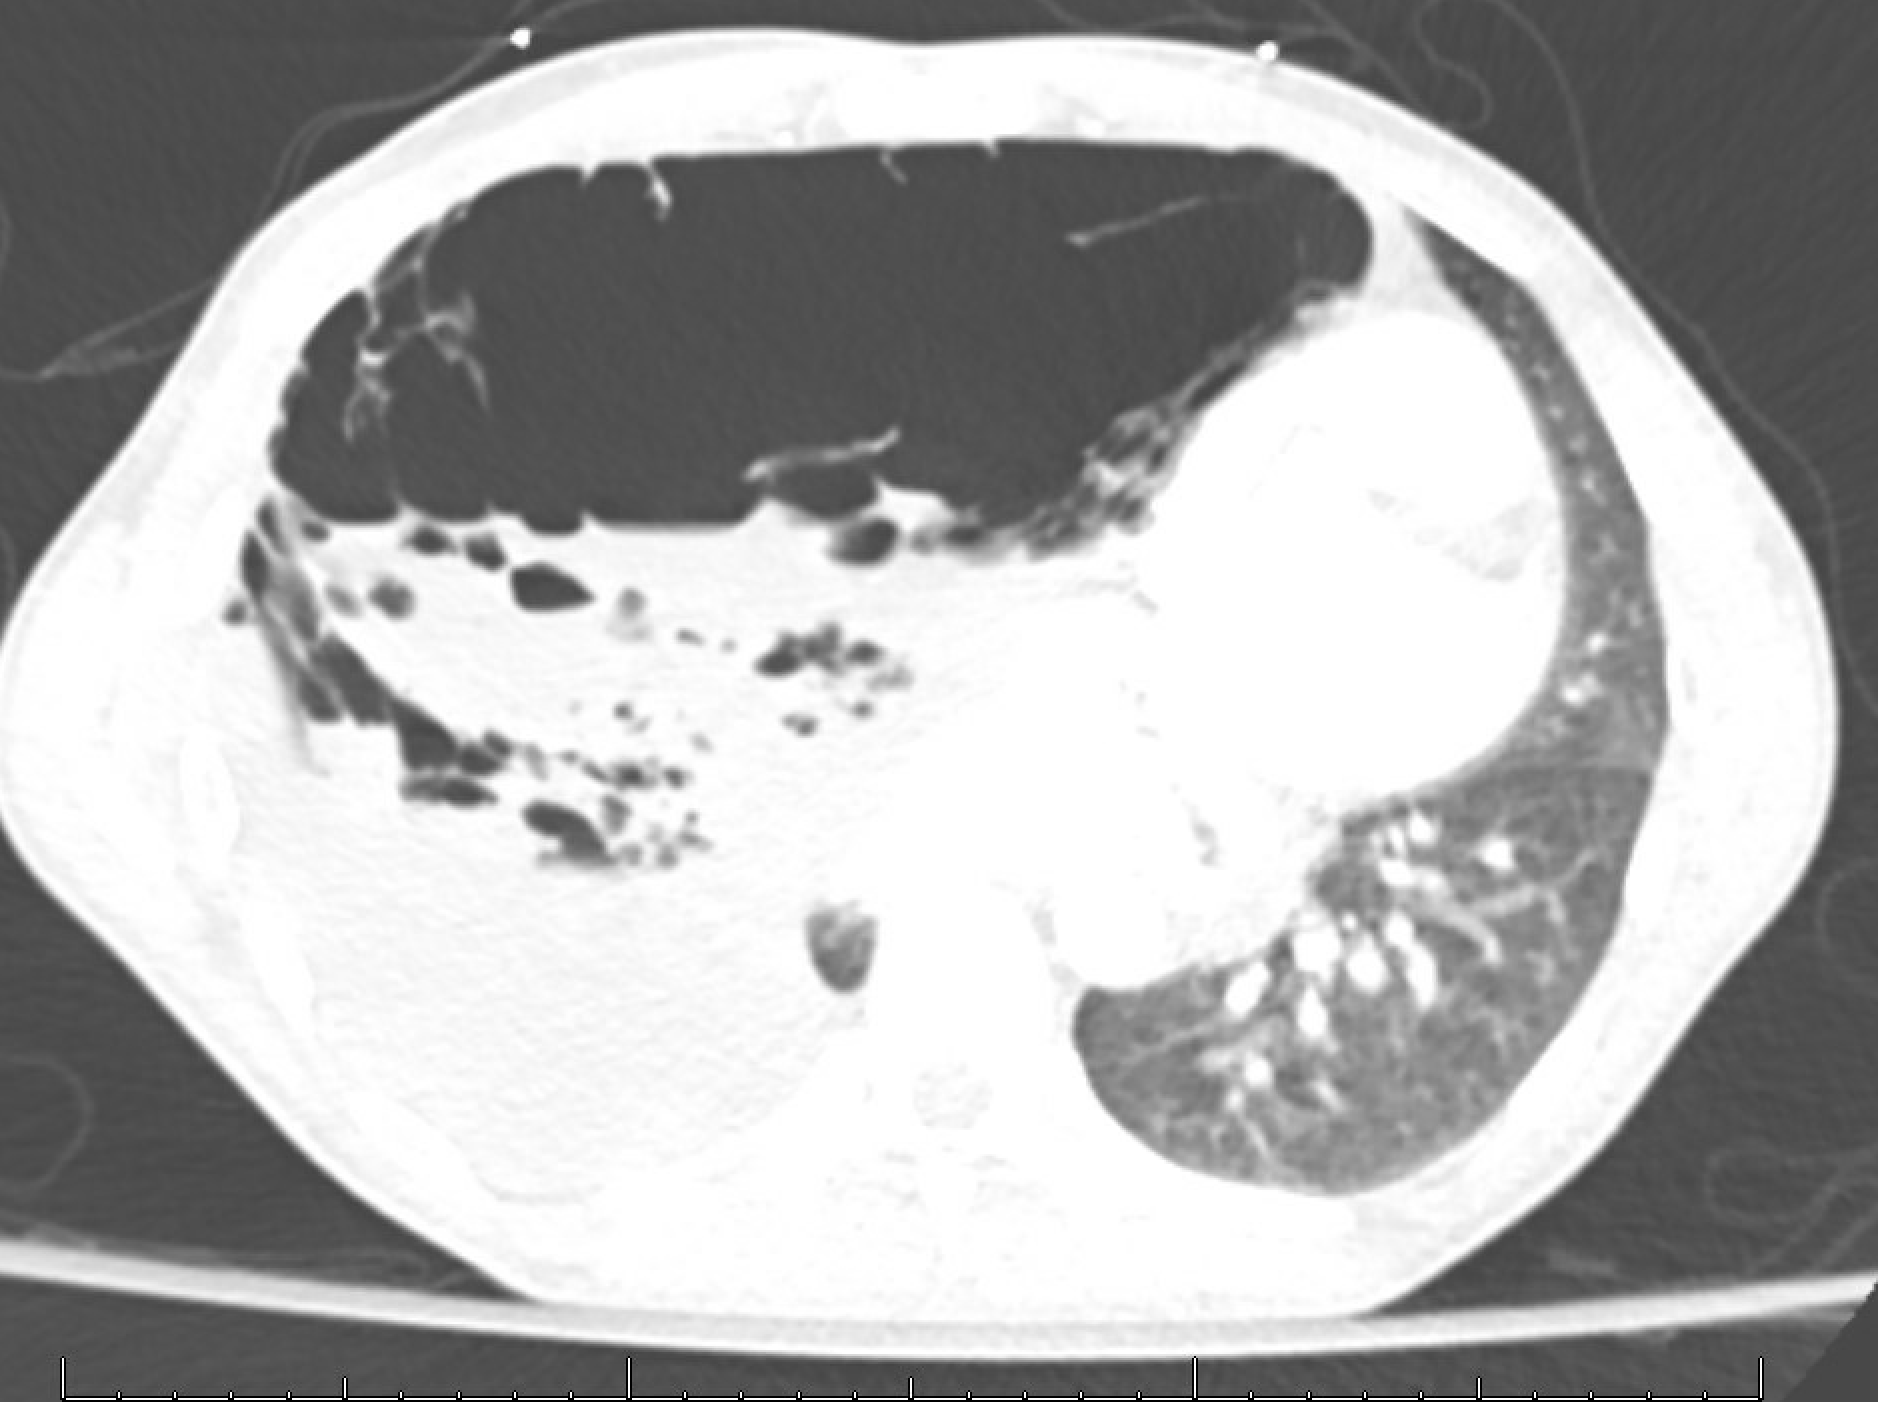

A 31-year-old man, non-smoker, no history of vaping without a known history of lung disease, presents with a 2-year history of progressive exertional dyspnea and cough with sputum production. Chest CT is shown above. Which of the following is the most likely cause of his condition?

A. Alpha-1 antitrypsin deficiency

B. Cystic fibrosis

C. Primary spontaneous pneumothorax

D. Vanishing lung syndrome

Return to this section next month for the answer!